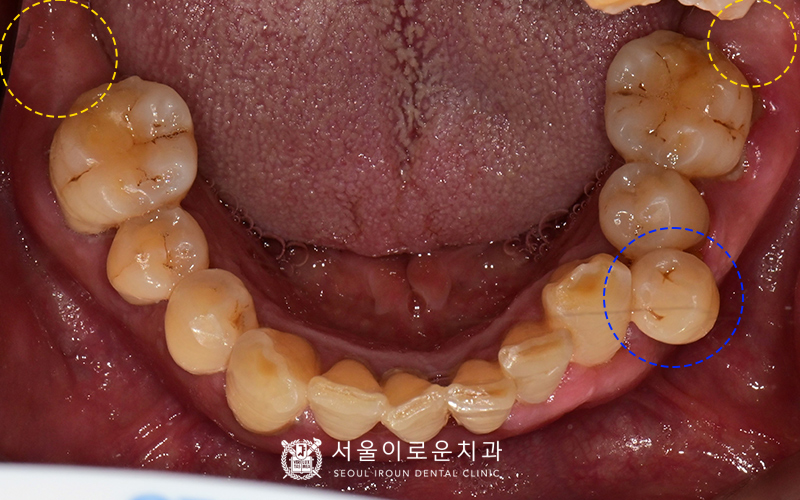

여러 각도에서 촬영한 구내사진입니다.

임상검사결과,

왼쪽 위 큰어금니와 아래 작은어금니 2개 모두

씹을 때 통증을 느끼시고

치아가 많이 흔들렸습니다.

환.자분의 경우, 치주염이 상당수 진행되어

잇몸이 많이 붓고 내려간 상태셨는데요.

특히, 왼쪽 아래 통증을 보이셨던

작은어금니 중

첫번째 작은 어금니 (#34)는

바깥쪽으로 자라난 상태셨는데요.

공간이 충분하지 않은 탓에

통증을 보였던 작은 어금니 두개 모두 발치 후에는

임플란트 한개만을 식립하여 보철치료를 하기로 계획하였습니다!